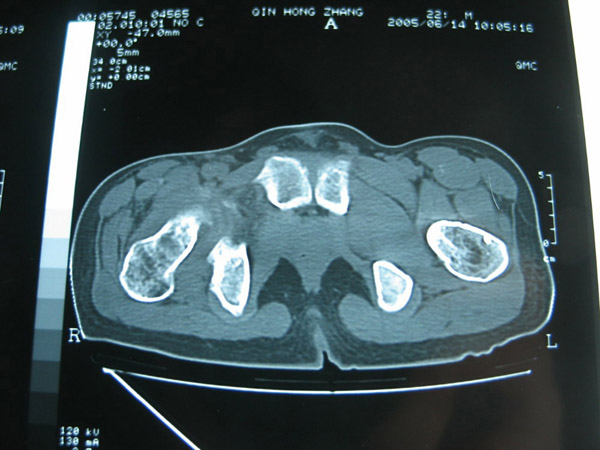

以下是引用hhcckk在2007-1-25 17:18:00的发言:[br][br]支持髋关节结核,[br]依据关节面破坏,有脓肿,脓腔内有钙化,关节周围增生不明显,鉴别[br]1化脓性的病变增生明显,临床上有高热[br]2创伤引起的关节炎,无菌坏死不会引起关节面的破坏,而且不会在这么短的时间内出现[br]

以下是引用卜一在2007-1-25 16:33:00的发言:[br]右侧髋关节股骨头及髋臼骨骨小梁疏松 粗糟,股骨头外形毛糟,软组织似肿胀,间隙略变窄.考虑:1 髋关节结核可能性大.2 缺血性坏死?3 化脓性髋关节炎?